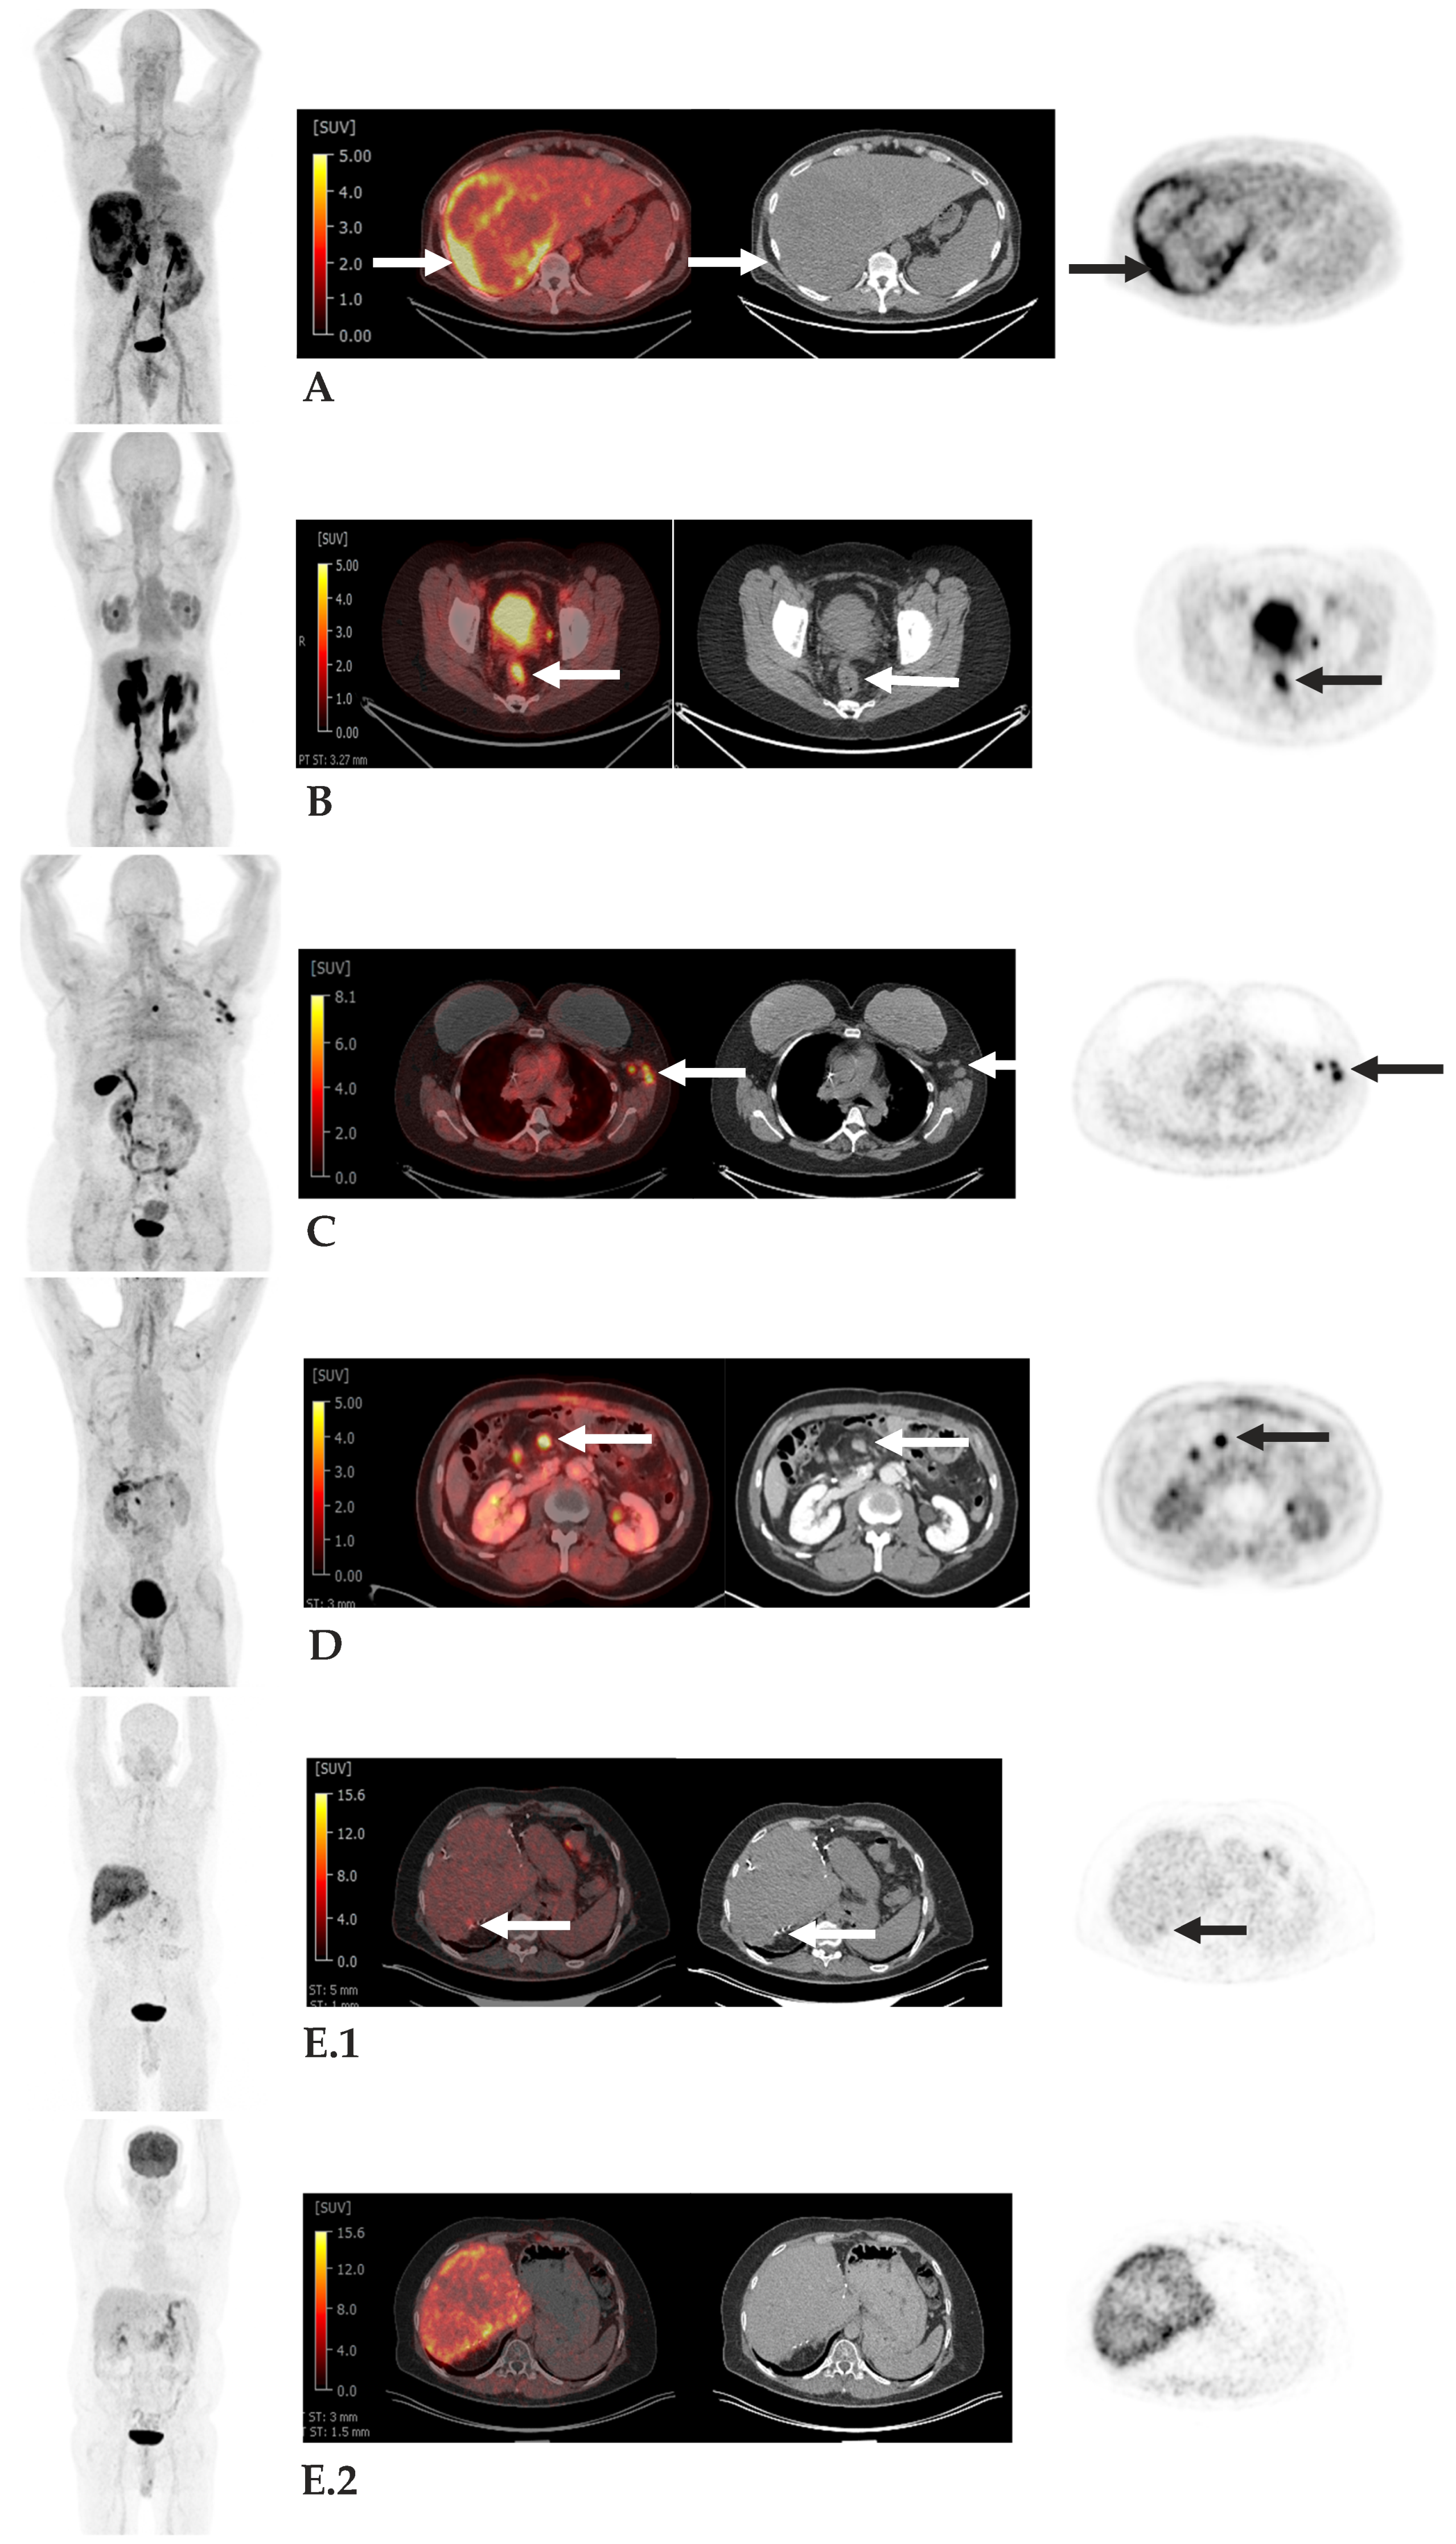

- Kratochwil, C.; Flechsig, P.; Lindner, T.; Abderrahim, L.; Altmann, A.; Mier, W.; Adeberg, S.; Rathke, H.; Röhrich, M.; Winter, H.; et al. (68)Ga-FAPI PET/CT: Tracer Uptake in 28 Different Kinds of Cancer. J. Nucl. Med. 2019, 60, 801–805. [Google Scholar] [CrossRef]

- Pang, Y.; Zhao, L.; Meng, T.; Xu, W.; Lin, Q.; Wu, H.; Zhang, J.; Chen, X.; Sun, L.; Chen, H. PET Imaging of Fibroblast Activation Protein in Various Types of Cancer Using (68)Ga-FAP-2286: Comparison with (18)F-FDG and (68)Ga-FAPI-46 in a Single-Center, Prospective Study. J. Nucl. Med. 2023, 64, 386–394. [Google Scholar] [CrossRef]

- Zhao, L.; Pang, Y.; Luo, Z.; Fu, K.; Yang, T.; Zhao, L.; Sun, L.; Wu, H.; Lin, Q.; Chen, H. Role of [(68)Ga]Ga-DOTA-FAPI-04 PET/CT in the evaluation of peritoneal carcinomatosis and comparison with [(18)F]-FDG PET/CT. Eur. J. Nucl. Med. Mol. Imaging 2021, 48, 1944–1955. [Google Scholar] [CrossRef]

- Assadi, M.; Rekabpour, S.J.; Jafari, E.; Divband, G.; Nikkholgh, B.; Amini, H.; Kamali, H.; Ebrahimi, S.; Shakibazad, N.; Jokar, N.; et al. Feasibility and Therapeutic Potential of 177Lu-Fibroblast Activation Protein Inhibitor-46 for Patients with Relapsed or Refractory Cancers: A Preliminary Study. Clin. Nucl. Med. 2021, 46, e523–e530. [Google Scholar] [CrossRef] [PubMed]

- Ferdinandus, J.; Costa, P.F.; Kessler, L.; Weber, M.; Hirmas, N.; Kostbade, K.; Bauer, S.; Schuler, M.; Ahrens, M.; Schildhaus, H.U.; et al. Initial Clinical Experience with (90)Y-FAPI-46 Radioligand Therapy for Advanced-Stage Solid Tumors: A Case Series of 9 Patients. J. Nucl. Med. 2022, 63, 727–734. [Google Scholar] [PubMed]

- Baum, R.P.; Schuchardt, C.; Singh, A.; Chantadisai, M.; Robiller, F.C.; Zhang, J.; Mueller, D.; Eismant, A.; Almaguel, F.; Zboralski, D.; et al. Feasibility, Biodistribution, and Preliminary Dosimetry in Peptide-Targeted Radionuclide Therapy of Diverse Adenocarcinomas Using (177)Lu-FAP-2286: First-in-Humans Results. J. Nucl. Med. 2022, 63, 415–423. [Google Scholar] [CrossRef]